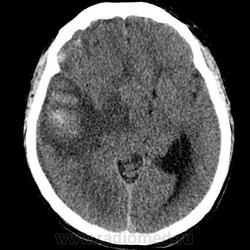

Я конечно никогда не работал на КТ и не описывал КТ снимки, но могу предположить, что имеется:

1. Оболочечная (субдуральная) гематома левой гемисферы мозга /гиподенсная, но выше чем ликвор в желудочках + значительный масс-эффект в виде сужения субарахноидальных пространств и борозд , деформации желудочковой системы и дислокации срединных структур/, явно не острая, может подострая.

2. Внутримозгая гематома (гиперденсная - значит острая стадия) в левой височной доле с наличием выраженного перифокального вазогенного отека и значительного масс-эффекта.

Согласен с предыдущим описанием. Внутримозговая гематома (острая), хроническая субдуральная гематома (скорее всего), надо смотреть по плотности, смещение срединных структур и сдавление желудочковой системы справа. Можно предположить разрыв АВМ. Контрастирование не проводили?

Прооперирован, сидит, разговаривает, ничего не помнит о том, как получил травму. Всё правильно, я тоже написала о субдуральной гематоме, объём 110 мл. Учитывая несколько гиперденсных участков в лобной части гематомы, вероятно, имело место повторная травма. Плотность гематомы преимущественно 25 ед.Н. Компрессия конвекситалов правой гемисферы субдуральной гематомой. Внутримозговая гематома 70 ед.Н в правой височной доле с перифокальным отёком, зона ушиба в правой лобной доле. Латеральная дислокация 2 см, выраженная, аксиальная дислокация. Асимметрия желудочков, выраженное смещение и деформация. Контрастирования не было.